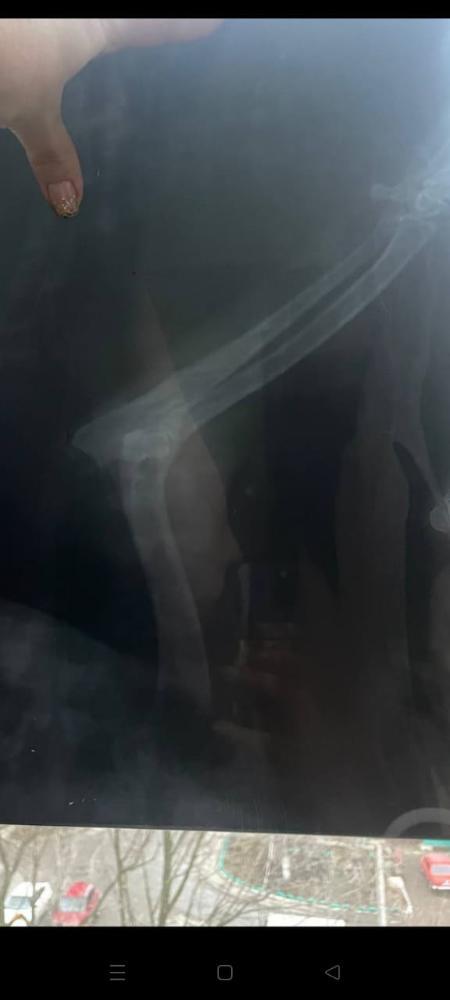

Кратко, нашли в январе 2024 , когда нашли не ходил, передняя лапа телепалась и шишка была на локте, не вставал на лапу, прокололи бонхарен, помогло. Сказали артроз.

Прикладываю старый рентген.